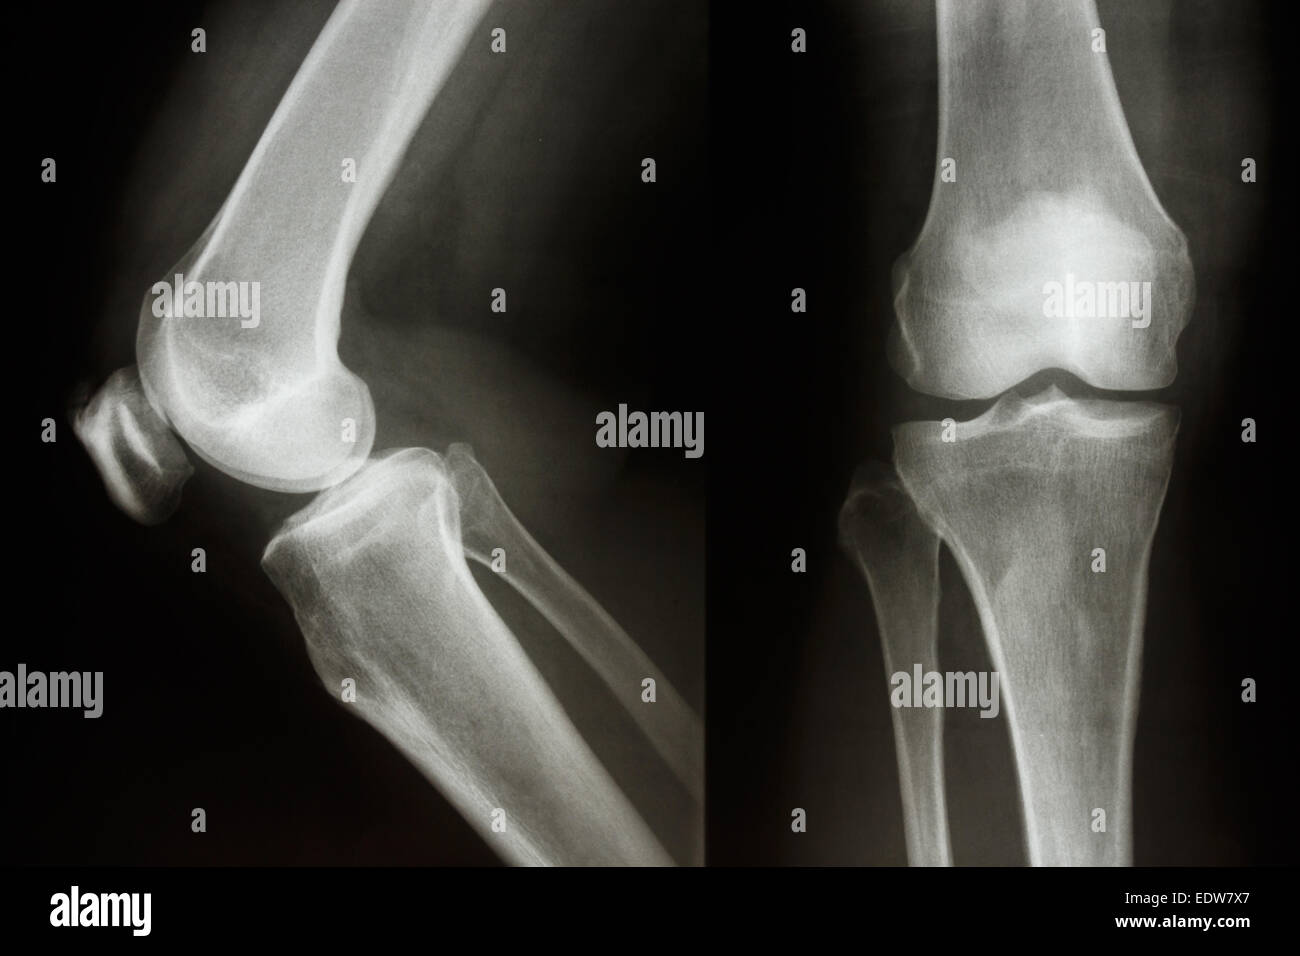

Flim X-ray latérale du genou : montrer l'articulation du genou humain normal Banque D'Imageshttps://www.alamyimages.fr/image-license-details/?v=1https://www.alamyimages.fr/photo-image-flim-x-ray-laterale-du-genou-montrer-l-articulation-du-genou-humain-normal-77253212.html

Flim X-ray latérale du genou : montrer l'articulation du genou humain normal Banque D'Imageshttps://www.alamyimages.fr/image-license-details/?v=1https://www.alamyimages.fr/photo-image-flim-x-ray-laterale-du-genou-montrer-l-articulation-du-genou-humain-normal-77253212.htmlRFEDK578–Flim X-ray latérale du genou : montrer l'articulation du genou humain normal

Film X-ray montrent l'articulation du genou normal(AP/latéral) Banque D'Imageshttps://www.alamyimages.fr/image-license-details/?v=1https://www.alamyimages.fr/photo-image-film-x-ray-montrent-l-articulation-du-genou-normal-ap-lateral-77387023.html

Film X-ray montrent l'articulation du genou normal(AP/latéral) Banque D'Imageshttps://www.alamyimages.fr/image-license-details/?v=1https://www.alamyimages.fr/photo-image-film-x-ray-montrent-l-articulation-du-genou-normal-ap-lateral-77387023.htmlRFEDW7X7–Film X-ray montrent l'articulation du genou normal(AP/latéral)